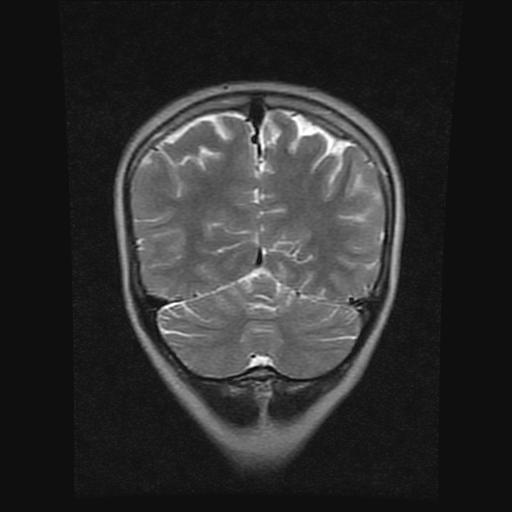

9岁女孩,三岁时诊断为癫痫,一直服丙戊酸钠,现患者一般情况良好,家长复查核磁片,看能否停药..

巨脑回